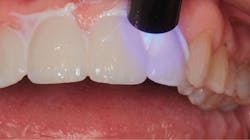

In 2016, she decided that she wanted to replace her veneers with the new bleach-shaded materials available today. In Figure 1, you can see her veneers as they appeared after nineteen years. Note the excellent tissue health and minimal tissue recession. There was a small fracture in the disto-incisal corner of the right central incisor. The incisal view at this date can be seen in Figure 2.

Figure 1: The patient’s porcelain laminate veneers placed in 1997 as seen in 2016